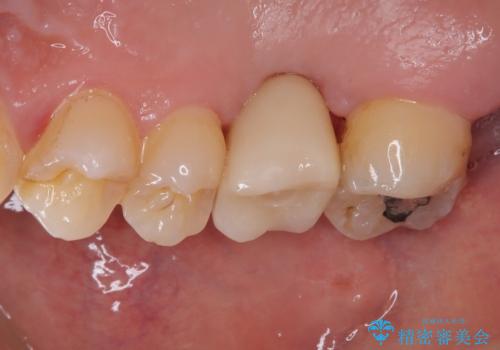

- 放置していたむし歯を治療したいとのことで来院された患者様です。

仕事が忙しいことを言い訳に虫歯を放置してきたものの、強い痛みを感じたことがあったため、重い腰を上げて来院されたとのことでした。

強い痛みのあった歯は、既に神経組織が失活しており根管治療が必要でした。

反対側の歯は、歯根だけが歯肉に埋もれて残っている状態のため、抜歯が必要な状態でした。